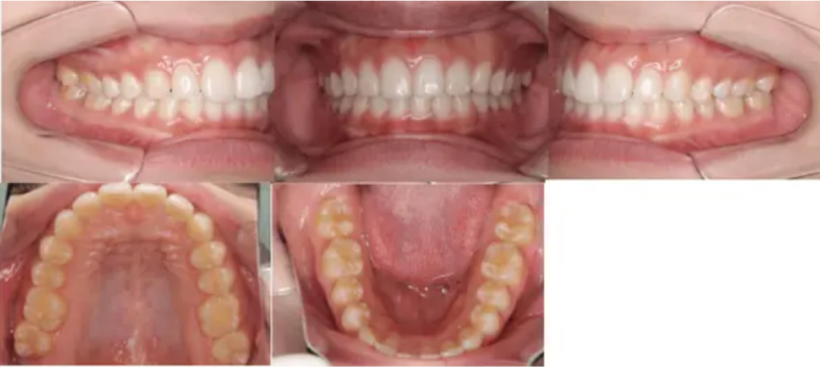

治療例①部分矯正: 28歳

| 主訴 | 前歯がガタガタである |

| 治療内容 | マウスピース型カスタムメイド矯正歯科装置(製品名インビザラインライト 完成物薬機法対象外)を使用して主訴である前歯の交叉咬合を改善しつつ、下あご前歯のガタガタも改善した。 |

| 治療期間 | 10カ月 |

| 費用 | 40万円 |

【治療前】